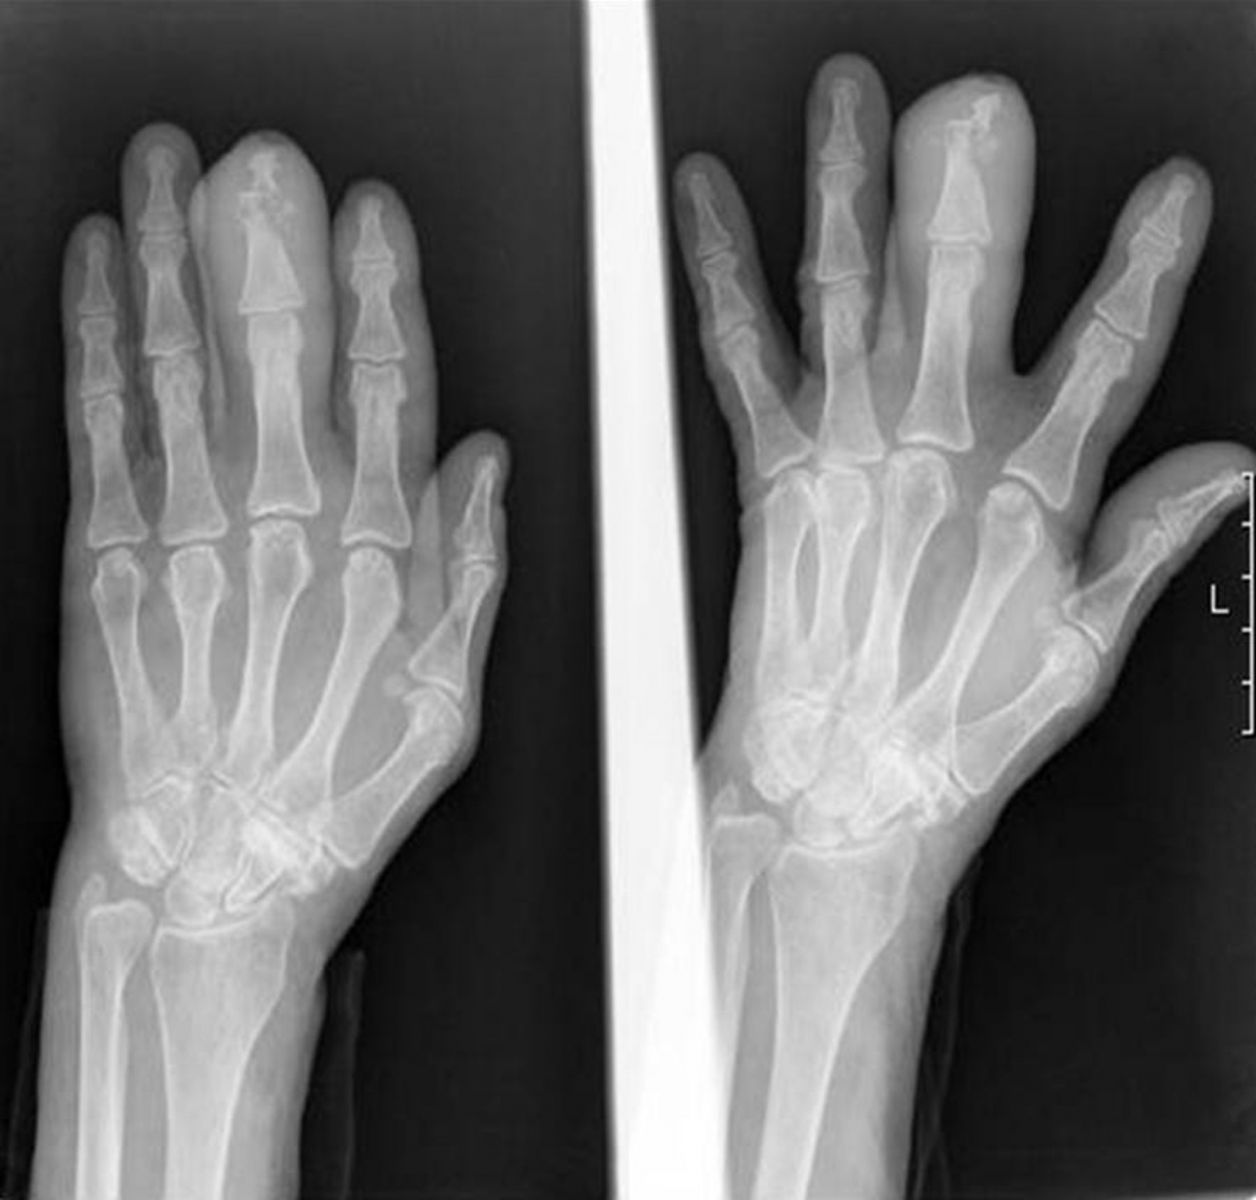

Инструментальная диагностика начинается с рентгенографии поражённого пальца в двух проекциях. Рентгенография пальцев применяется для выявления очагов костной деструкции, периостальных реакций и патологических изменений, возникающих при воспалении костной ткани. Исследование проводится в прямой и боковой проекциях, охватывая весь палец с окружающими мягкими тканями. При наличии свищей, секвестров или подозрения на обширный гнойный процесс используется прицельная рентгеноскопия с контрастированием свищевых ходов. Комплексная визуализация позволяет выявить как острое, так и хроническое течение остеомиелита.

Рентген выявляет следующие анатомические признаки:

- Очаги остеолиза в фалангах, визуализирующиеся как зоны просветления с размытыми краями, соответствуют разрушению костной ткани в зоне воспаления.

- Субпериостальные наслоения, преимущественно по тыльной поверхности проксимальных фаланг, указывают на реакцию надкостницы и характерны для перехода в хроническую стадию.

- Секвестры определяются как плотные обособленные участки внутри зоны остеопороза — типичный признак длительно текущего гнойного остеомиелита.

- Контуры фаланг становятся неровными, с деформацией суставных поверхностей и укорочением длины, что отражает прогрессирующее разрушение при хроническом процессе.

- При рентгеноскопии с контрастом визуализируется симптом «контрастного свища» — распространение вещества по узкому ходу, соединённому с деструктивной полостью внутри кости.

Рентгенологическое исследование позволяет детально визуализировать следующие диагностические параметры:

- Наличие остеолитических изменений в фалангах с чёткой локализацией очага позволяет подтвердить воспаление и определить его распространённость.

- Обнаружение секвестров и зон остеосклероза указывает на хроническое течение с формированием некротических участков, требующих хирургической обработки.

- Периостальная реакция, выражающаяся в виде плотных костных наслоений, помогает отличить остеомиелит от других форм деструкции, включая опухолевые и травматические поражения.

- Контрастное исследование свищевых ходов позволяет точно определить их направление и связь с костной полостью, что имеет значение при планировании оперативного вмешательства.